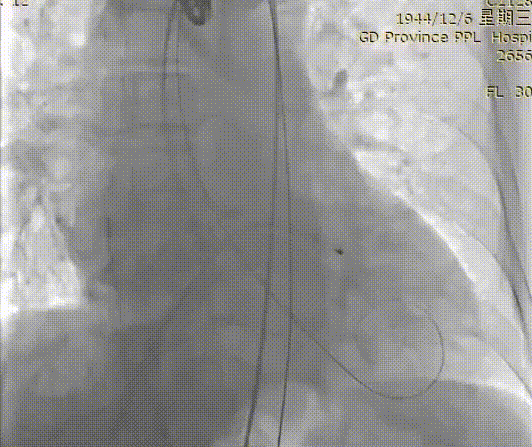

主动脉根部造影

交换猪尾测得

主动脉压力87/32mmHg

左心室压力135/8mmHg

压差48mmHg

VitaFlow®可回收输送系统过弓

24 mm球囊预扩

VitaFlow®第一次定位

释放2/3后造影确认位置

回收后再次定位

再次造影确定位置

释放瓣膜